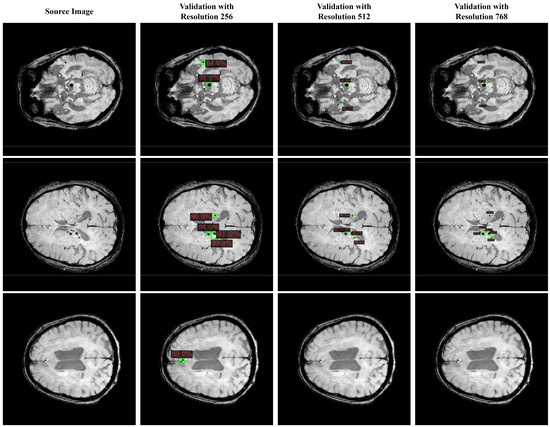

| Model Name | Backbone | Train Resolution | Validation Resolution | P | R | ||

|---|---|---|---|---|---|---|---|

| ConvNeXt | S | 0.80 | 0.66 | 0.76 | 0.49 | ||

| 0.83 | 0.75 | 0.81 | 0.52 | ||||

| 0.88 | 0.77 | 0.82 | 0.54 | ||||

| 0.82 | 0.57 | 0.74 | 0.43 | ||||

| 0.86 | 0.74 | 0.82 | 0.52 | ||||

| 0.89 | 0.81 | 0.85 | 0.57 | ||||

| DINO | R50 | 0.91 | 0.85 | 0.86 | 0.61 | ||

| 0.92 | 0.89 | 0.88 | 0.64 | ||||

| 0.92 | 0.88 | 0.87 | 0.64 | ||||

| 0.89 | 0.88 | 0.86 | 0.63 | ||||

| 0.92 | 0.91 | 0.87 | 0.64 | ||||

| 0.93 | 0.91 | 0.89 | 0.66 | ||||

| YOLOv8 | X6 | 0.83 | 0.74 | 0.76 | 0.52 | ||

| 0.91 | 0.78 | 0.86 | 0.55 | ||||

| 0.92 | 0.78 | 0.85 | 0.54 | ||||

| 0.81 | 0.72 | 0.75 | 0.49 | ||||

| 0.88 | 0.79 | 0.85 | 0.56 | ||||

| 0.92 | 0.81 | 0.88 | 0.57 | ||||

| CMBs-YOLO | X6 | 0.88 | 0.81 | 0.85 | 0.57 | ||

| 0.93 | 0.86 | 0.91 | 0.62 | ||||

| 0.94 | 0.87 | 0.90 | 0.61 | ||||

| 0.86 | 0.83 | 0.83 | 0.55 | ||||

| 0.93 | 0.88 | 0.90 | 0.62 | ||||

| 0.95 | 0.89 | 0.92 | 0.62 |